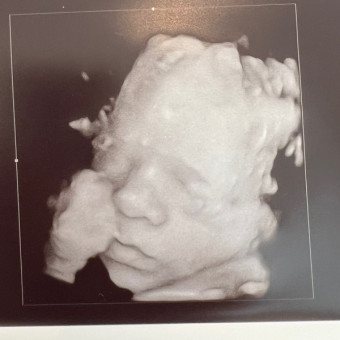

Giovanni

Emily & Joe Bollero

I am in disbelief and excitement that this third (and final) pregnancy is coming to an end!! YIPPEE!! We cannot wait to meet baby Gio!! The boys are beyond excited and I have started nesting. So with that being said, after going through some stuff in the basement, this list was created with intent of what I "need." Truly, I feel blessed to say that we are not in need of anything but it was fun to get the boys excited and pick things out for their much anticipated baby brother.